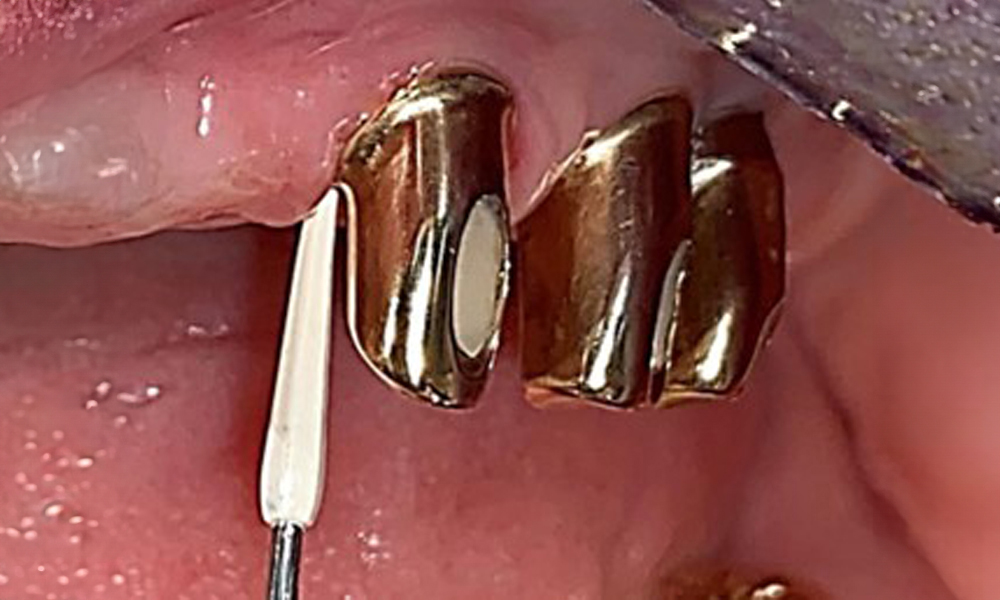

Der dentale Befund stellt sich wie folgt dar: Kombinierte herausnehmbare Implantat- und zahngetragene Teleskoparbeit auf Implantaten 15, 13, 21, 23, 24, 25 und Zahn 11 (Abb. 1, Abb. 2, Abb. 3). Im Unterkiefer ist die Patientin mit einem festsitzenden Zahnersatz versorgt. 37–34 sowie 45–47 haben suffiziente Brücken (Abb. 4). Kronenränder sind intakt, aktive kariöse Läsionen sind nicht vorhanden. An Zahn 43 zeigt sich eine Compositefüllung mit Randspalt. Im Unterkiefer liegen Rezessionen mit freiliegender Wurzeloberfläche zwischen 1 – 3 mm vor. Dies trifft auch für 11 zu.

Okklusalansicht: Oberkiefer mit Zahn- und implantatgetragenen Teleskopen.

Abb. 2: Okklusalansicht: Oberkiefer mit Zahn- und implantatgetragenen Teleskopen.